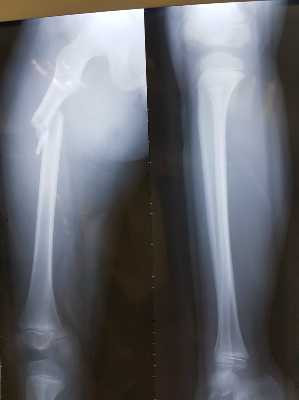

Cháu Kiên được kết luận gãy xương đùi, bó bột, nhưng sau đó xương không khớp. Gia đình đã đưa Kiên sang Bệnh viện Việt Đức để mổ và nẹp vít xương.

Hình ảnh chụp X quang vị trí gãy xương của cháu Trần Chí Kiên - Ảnh gia đình cung cấp

Anh Dũng cho biết 5 ngày điều trị tại Bệnh viện Việt Đức, bác sĩ đánh giá chấn thương của cháu Kiên là nghiêm trọng, ảnh hưởng đến nhiều chức năng của cháu sau này.

Khi nghe gia đình trình bày nguyên nhân cháu chơi và tự ngã ở sân trường thì bác sĩ khẳng định "việc chạy và tự ngã không thể gây ra chấn thương nặng như vậy" vì xương đùi rất khó gãy nếu không có lực rất mạnh tác động. Cháu Kiên không có bệnh lý gì về xương.